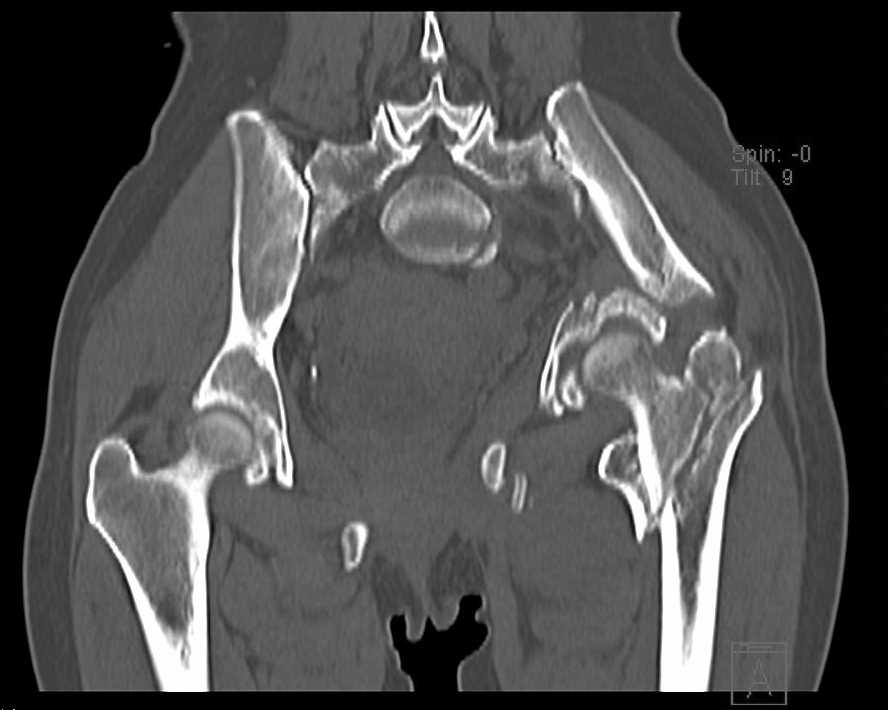

Больная 43 года (промышленный альпинист), 28.07.08 в результате падения с 5 этажа получила политравму: Перелом свода и основания черепа. Вертикально-нестабильное повреждение таза, осложнённое разрывом мочевого пузыря. Чрезвертельный перелом левого бедра. Перелом правой таранной кости, переломовывих правой кубовидной кости. Тупая травма живота, разрыв печени, ушиб почек. Забрюшинная гематома. В день травмы - лапаротомия, ушивание ран печени. Разрыв мочевого пузыря не диагностирован. Течение болезни осложнилось развитием мочевого затёка и обширной пред- и забрюшинной флегмоны, сформировался свищ мочевого пузыря. 19.8.2008 вскрытие, дренировние флегмоны, ревизия мочевого пузыря, обтурация мочевого свища (свищ закрылся в октябре), 1.10.2008 некрэктомия, пластика по Шеде-Лидскому правой кубовидной кости. По результатам КТ диагностирован рак правой почки (диагностическая находка), 8.10.2008 нефрэктомия справа. Переломы велись консервативно. Имеется вертикальное смещение левой половины таза с выраженным отведением крыла (клинически подвижности нет), несросшийся низкий двухколонный перелом левой вертлужной впадины с потерей конгруэнтности, укорочение около5 см, застарелый разрыв лонного сочленения, неправильно сросшиеся переломы обеих ветвей правой лонной кости с укорочением, патологическая подвижность лоно-седалищного фрагмента слева. Правая нижняя конечность неопорна, несмотря на то, что лежа прямую ногу поднимает, ходит на левой ноге (ортопедическая обувь) с костылями, справа тазобедренный ортез. Седалищные нервы работают.Урологи отпустили больную на 6 мес.